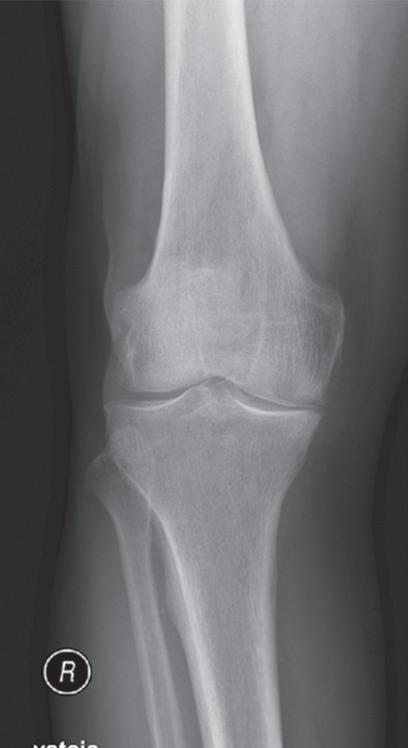

Základem diagnózy je klinické vyšetření doplněné o rentgenový snímek obvykle ve dvou projekcích

Obr. 19.2: Varózní deformita pravého kolenního kloubu (levé koleno již po korekci osy v rámci implantace náhrady kolenního kloubu) – (a) a rentgenový nález úhlové deformity s nálezem pokročilých artrotických změn (b)

(předozadní a bočná). Na rentgenovém snímku se gonartróza zpočátku projevuje přihrocením interkondylické eminence a subchondrální sklerózou v místě přetížení, později zúžením, případně až zánikem kloubní štěrbiny, vznikem osteofytů, pseudocyst a případnou úhlovou deformitou. Dle nálezu rovněž klasifikujeme stupeň gonartrózy podle Kellgrena-Lawrence (viz kap. 17, obr. 19.4), což má praktický význam v indikaci farmakoterapie i balneoterapie.